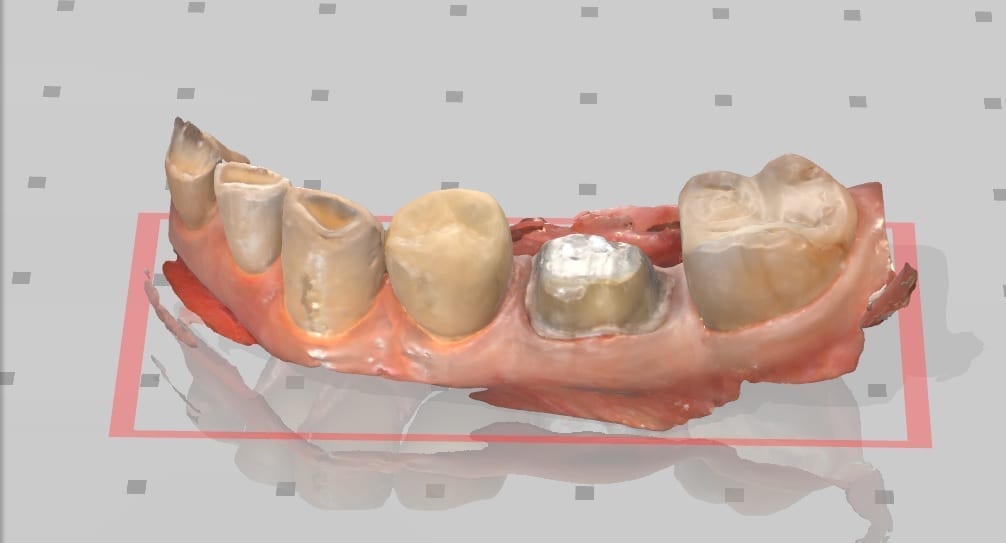

This is an upper and lower case that is scanned with the Medit i500 intra-oral scanner. The lower arch was prepared first and imaged and saved. Then the upper molar was prepared and scanned as well. The bite was captured from the buccal while the patient was biting down in maximum intercuspation. Tissue retraction was not necessary in either case as we could discern the margins simply by the color difference between the tooth structure and the tissue.

Image of case exported as OBJ

Delivery of the restorations, fabricated by Burbank Dental Lab. There were no adjustments made to the contacts or to the occlusion.